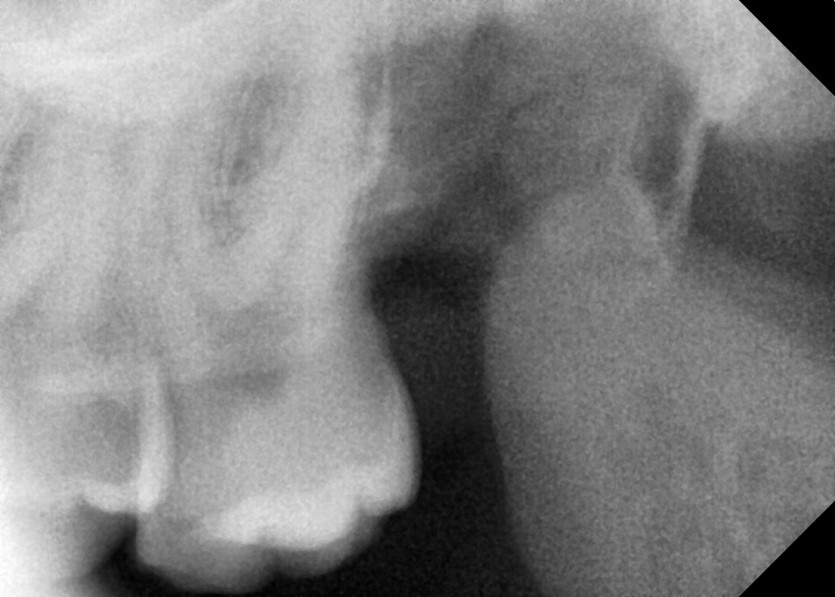

#18,28,38,48 사랑니 발치

구강 외과 전문의가 당일 발치했습니다.